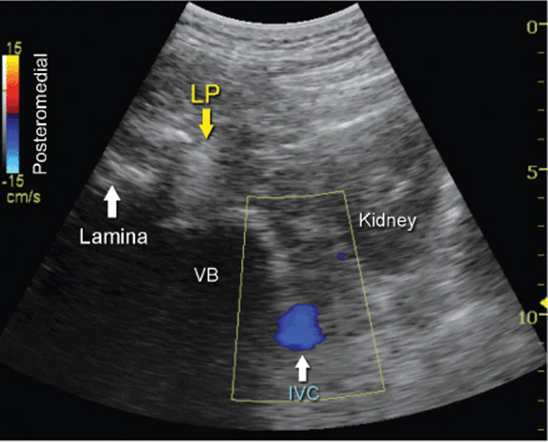

Kirchmair and colleagues were among the first to describe the sonoanatomy of relevance for LPB.3 They reported the ability to accurately guide a needle to the posterior part of the psoas muscle, where the roots of the lumbar plexus are located, using ultrasound guidance in cadavers.4,5 Since, significant advances in ultrasound technology have taken place, allowing for much improved image quality, which have allowed Karmakar and colleagues to devise an alternative approach to the lumbar plexus using ultrasonographic identification of the transverse processes as the guide.6 With this scanning technique, the transducer is positioned 4 to 5 cm lateral to the lumbar spinous process at the L3-L4 level and directed slightly medially to assume a transverse oblique orientation (Figure 46-4). This approach allows imaging of the lumbar paravertebral region with the erector spinae muscle, transverse process, the psoas major muscle, quadrates lumborum, and the anterolateral surface of the vertebral body (Figure 46-5A, B, and C). In the transverse oblique view, the inferior vena cava (IVC), on the right-sided scan, or the aorta, on the left-sided scan, also can be seen and provide additional information on the location of the psoas muscle, which is positioned superficial to these vessels. In this view, the psoas muscle appears slightly hypoechoic with multiple hyperechogenic striations within. The lower pole of the kidney can often be seen, when scanning at the L2-L4 level, as an oval structure that ascends and descends with respirations (Figure 46-6). The key to obtaining adequate images of the psoas muscle and lumbar plexus with the transverse oblique scan is to insonate between two adjacent transverse processes. This scanning method avoids acoustic shadow of the transverse processes, which obscures the underlying psoas muscle and the intervertebral foramen (angle between the transverse process and vertebral body) and allows visualization of the articular process of the facet joint (APFJ) as well. Because the intervertebral foramen is located at the angle between the APFJ and vertebral body, lumbar nerve roots often can be depicted.

FIGURE 46-6. Ultrasound image of the lumbar paravertebral space demonstrating the complex anatomy of the region. LP, lumbar plexus; VB, vertebral body. Power Doppler ultrasound is capturing the flow in the inferior vena cava (IVC). The right kidney is also visualized.